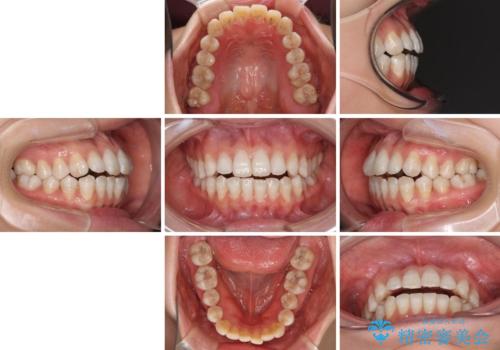

話しにくいオープンバイト インビザラインによる矯正治療

- 前歯の上下スペースによる話しにくさを気にして来院された患者様です。

インビザラインにより上下の前歯の隙間を閉じていくこととしました。

上下の奥歯を圧下させるようにすることで、前歯を接触させるように計画しました。

隙間に舌が入り込むことが話しにくさに繋がっていたため、舌の筋肉のトレーニングも並行して行い、話しにくさの改善と後戻りの抑制を図りました。